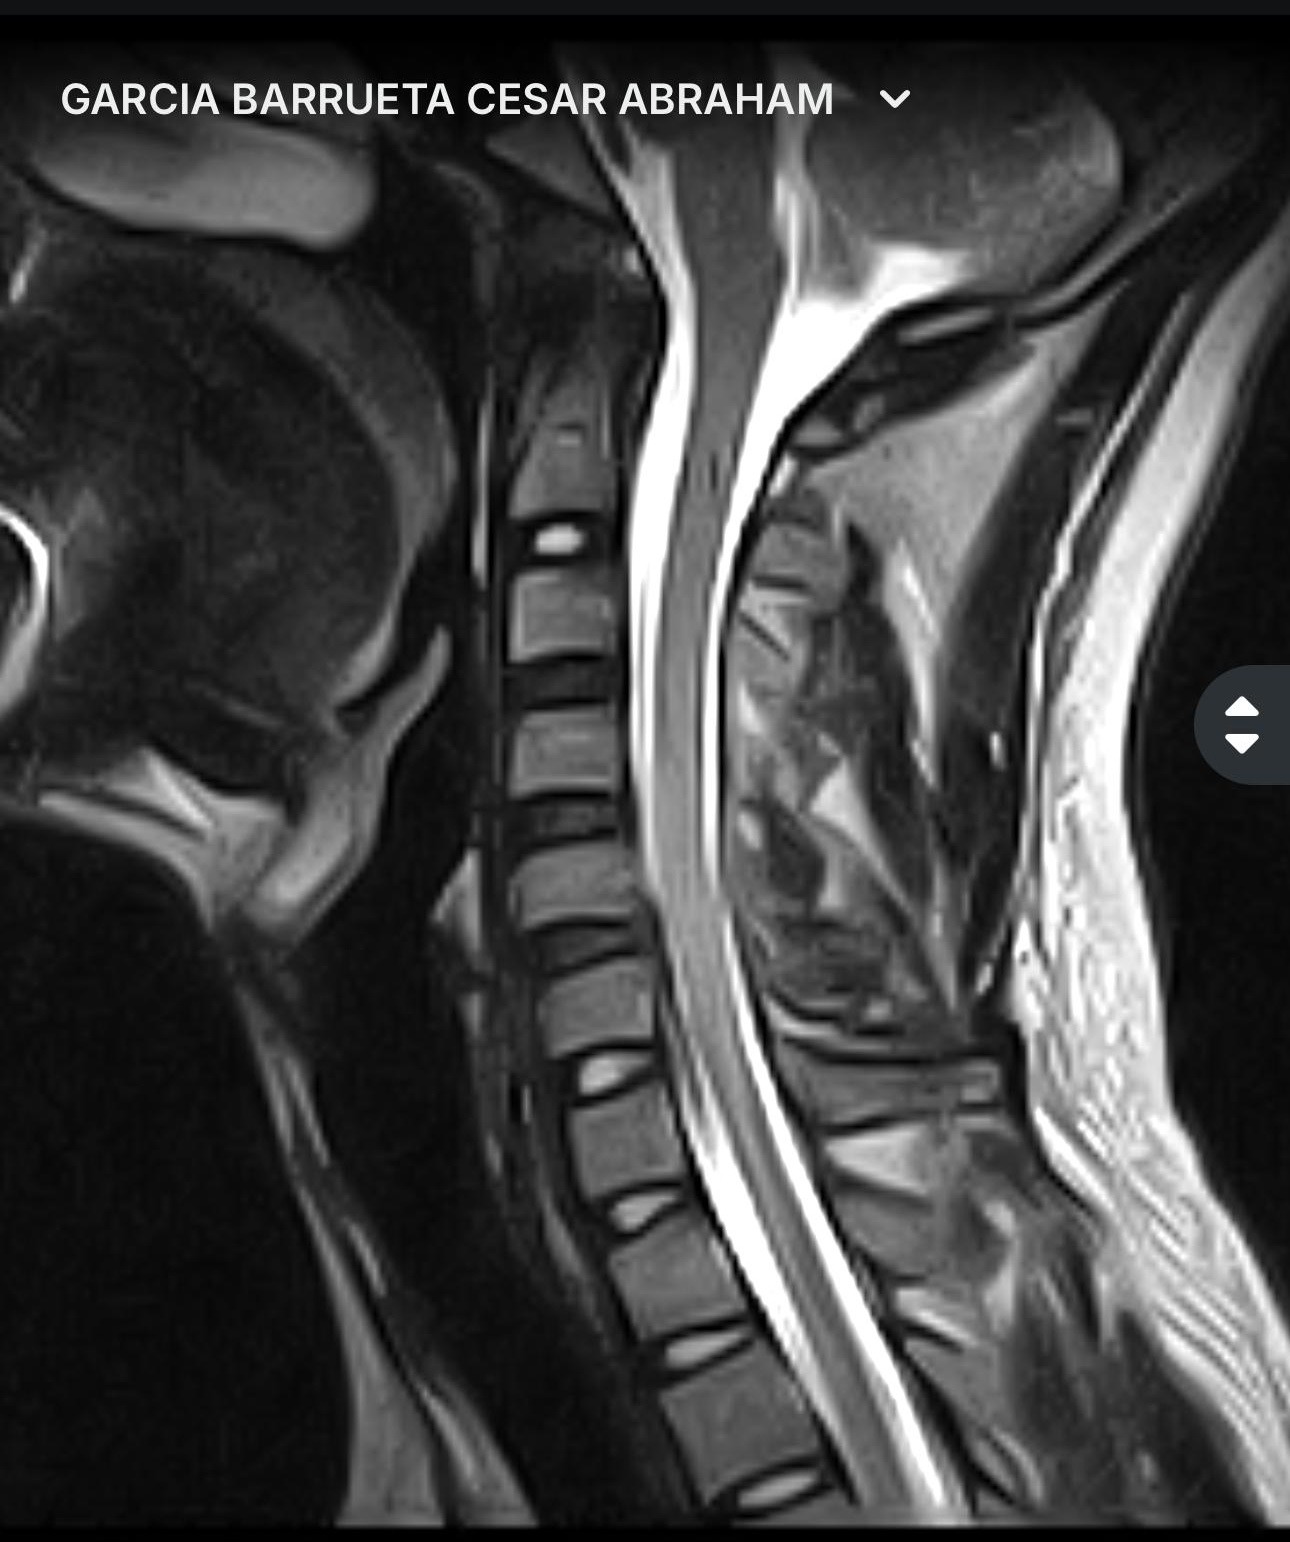

El dolor en el hombro no se calmo, el entumecimiento sigue actualmente en mi brazo izquierdo hacia el dedo pulgar, por lo que me realice una RM donde un neurólogo clínico y el neurocirujano especialista en columna, me diagnosticaron una protrusion discal en C6 con migración hacia abajo, que comprime el cordón medular, el agujero de conjunción derecho estrecho en C5 C5 lo que significa una subluxación facetaria, afortunadamente no pasó a mayores y sigo con movilidad en todos los miembros, pero tengo problemas de sensibilidad en el brazo izquierdo. Por eso requiero de esta cirugía de extirpación del disco intervertebral con estabilización espinal para corregir la subluxación.